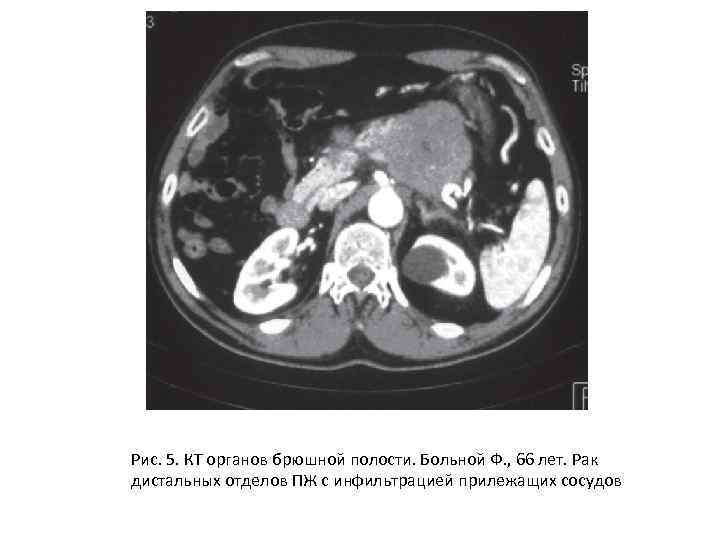

Рис. 5. КТ органов брюшной полости. Больной Ф. , 66 лет. Рак дистальных отделов ПЖ с инфильтрацией прилежащих сосудов